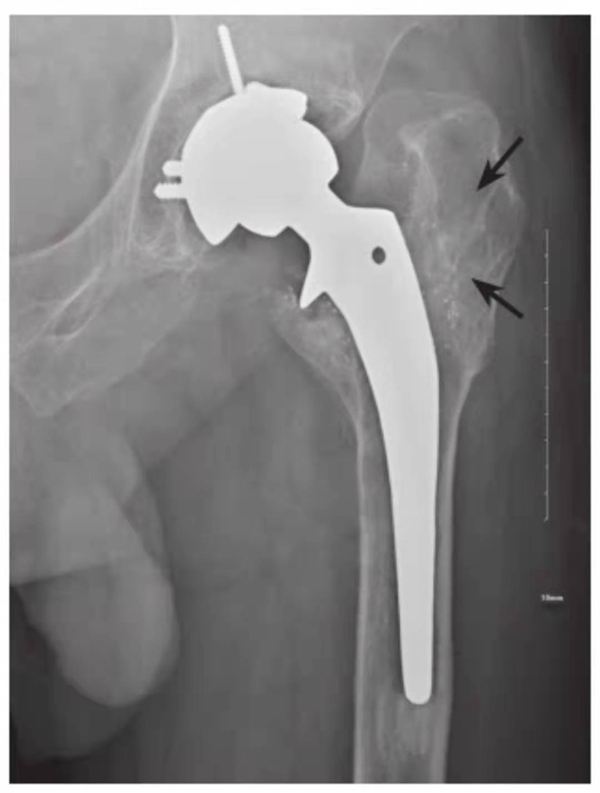

图3 无菌性松动

平片,示右侧髋臼杯周围骨质吸收,髋臼杯松动并向上内侧移位